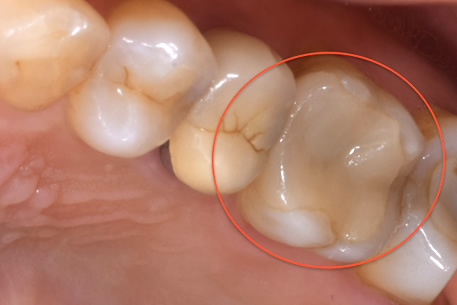

治療前

見た目では全くわかりませんが、レントゲンでは黒く抜けて虫歯になっていることがわかります。

虫歯の見分け方

治療中

治療中①

治療中②

治療中①:つめ物をとったところ。茶色い部分は虫歯になっている。

治療中②:染色液を用いて虫歯を選択的に取り除いた。歯はかなりなくなっており、神経近くまで進行していた。

経過観察

虫歯を取り除いた後、神経を守るためのお薬をつめて、2ヶ月ほど経過観察をした。

治療後

経過観察中に症状がでなかったため、セラミックのつめ物をいれていった。